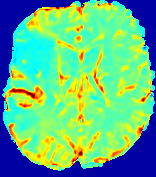

LesionRefer to captionRefer to captionRefer to captionRefer to captionRefer to captionRefer to caption𝐕rgbsubscript𝐕𝑟𝑔𝑏{\bf{V}}_{rgb}Refer to captionRefer to captionRefer to captionRefer to captionRefer to captionRefer to caption𝐕2subscriptnorm𝐕2{\|\bf{V}}\|_{2}Refer to captionRefer to captionRefer to captionRefer to captionRefer to captionRefer to captionRefer to caption3.53.53.52.82.82.82.12.12.11.41.41.40.70.70.70.00.00.0(mm/s)𝑚𝑚𝑠(mm/s)D𝐷DRefer to captionRefer to captionRefer to captionRefer to captionRefer to captionRefer to captionRefer to caption0.0200.0200.0200.0160.0160.0160.0120.0120.0120.0080.0080.0080.0040.0040.0040.0000.0000.000(mm2/s)𝑚superscript𝑚2𝑠(mm^{2}/s)Slice #1Slice #2Slice #3Slice #4Slice #5Slice #6

Figure 3: PIANO feature maps for one stroke patient, where the lesion is located in the left hemisphere. Top row: segmented stroke lesion region (white) on different slices, obtained from ISLES 2017. The corresponding slices for the PIANO feature maps are shown in the following rows.

For a better insight into an estimated velocity field 𝐕𝐕{\bf{V}} and diffusion field 𝐃𝐃{\bf{D}}, we compute the following maps: (1) 𝐕rgbsubscript𝐕𝑟𝑔𝑏{\bf{V}}_{rgb}: Color-coded orientation map of 𝐕=(Vx,Vy,Vz)T𝐕superscriptsuperscript𝑉𝑥superscript𝑉𝑦superscript𝑉𝑧𝑇{\bf{V}}=(V^{x},V^{y},V^{z})^{T}, obtained by normalizing 𝐕𝐕{\bf{V}} to unit length and mapping its 3 components to red, green, blue respectively; (2) 𝐕2subscriptnorm𝐕2\|{\bf{V}}\|_{2}: 222 norm of 𝐕𝐕{\bf{V}}; (3) D𝐷D: scalar field in Eq. 5.

Fig. 3 and Fig. 4 show the PIANO feature maps estimated from two ISLES 2017 patients: all are highly consistent with the lesion in both cases. Details of the blood flow trajectories are revealed in 𝐕rgbsubscript𝐕𝑟𝑔𝑏{\bf{V}}_{rgb} by the ridged patterns and the sharp changes of colors in the unaffected (right) hemisphere, while the flat patterns appearing within the lesion provide little directional information about the velocity and indicate low velocity magnitudes. Velocity magnitudes are more directly visualized via 𝐕2subscriptnorm𝐕2\|{\bf{V}}\|_{2}, from which one can easily locate the lesion where 𝐕2subscriptnorm𝐕2\|{\bf{V}}\|_{2} is low. D𝐷D also indicates lower diffusion values in the lesion, though with less contrast potentially due to the fact that it captures the accumulated effect of CA diffusion at the voxel-level.